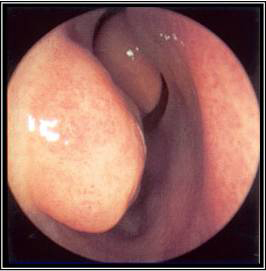

[Figure caption and citation for the preceding image starts]: Meato médio esquerdo com edema grave e secreções purulentasDo acervo de Melissa Pynnonen, MD [Citation ends].

[Figure caption and citation for the preceding image starts]: Meato médio esquerdo com mucosa saudável e secreções não purulentasDo acervo de Melissa Pynnonen, MD [Citation ends].